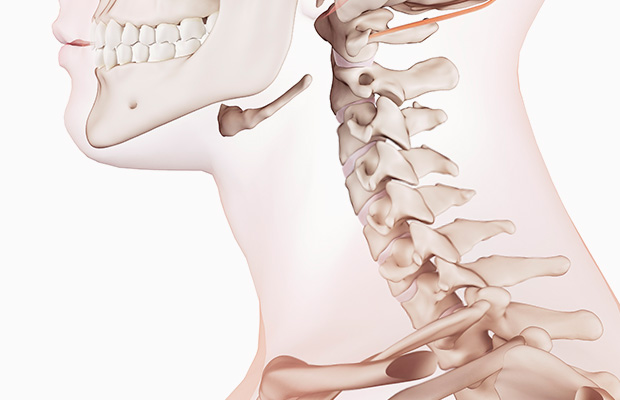

목디스크의 증상은 여러종류가 있으며 환자마다 그 증상이 같지않게 생겨날수 있습니다. 최고 흔한 증상으로는 목의 통증입니다. 목의 통증은 목 뒤쪽, 어깨, 팔, 손까지 뻗쳐서 일어날 수 있습니다. 거기에다가, 저림, 마비, 감각 이상, 손발의 힘 저하 등의 증상이 발생할 수 있습니다.

많은 종류의 사고 및 스포츠 관련 부상으로 인한 목 외상은 목 디스크에 과격한 손상을 유발할 수 있습니다. 또한 목을 갑작스럽고 강하게 움직이면 디스크가 찢어지거나 탈출할 수 있기에 이러한 부상을 입지 않을수 있게 조심하는 것이 필요합니다.